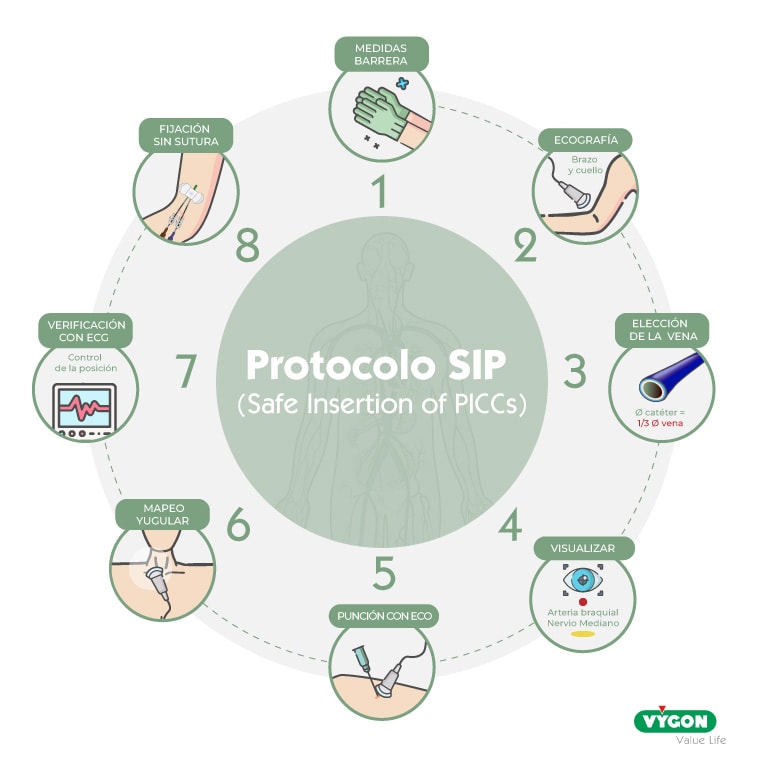

¿No tienes tiempo de leértelo todo? No pasa nada, ahí van los distinos pasos resumidos:

- Paso 1: técnica totalmente estéril que requiere lavado de manos, uso de indumentaria completa estéril, campos estériles que cubren el paciente, uso de clorhexidina al 2%

- Paso 2: exploración de las venas del brazo y del cuello con el ecógrafo con el método RaPeVa

- Paso 3: elección de la mejor vena: correcta ubicación (profundidad, alejada de nervios y arterias), que se colapse y que tenga un diámetro adecuado

- Paso 4: identificación del nervio mediano y de la arteria braquial

- Paso 5: punción ecoguiada con técnica Microseldinger

- Paso 6: control ecográfico de la vena yugular durante el progreso del catéter

- Paso 7: comprobación de la posición de la punta del catéter mediante ECG

- Paso 8: fijación con un sistema sin sutura, cianocrilato en el punto de punción y cubrir con un apósito transparente

El protocolo SIP (Inserción Segura de PICCs) fue creado hace casi 10 años por el grupo GAVeCeLT en su afán de compartir una metódica estandarizada y basada en evidencia científica para la inserción de PICC. Los veloces avances en este campo han hecho que ya hoy contemos con la segunda versión de este protocolo cuyo objetivo, no es solo la colocación correcta de PICC, sino, también, la reducción de complicaciones.

El protocolo SIP se compone de 8 pasos. Lo presentamos aquí como en su versión de 2014, aunque con los años se ha visto modificado en algunos detalles que han sido incluidos en esta descripción: